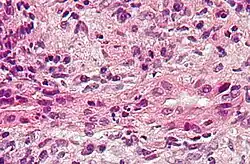

Cirrose biliar primária (atualmente colangite biliar primária), muitas vezes abreviada CBP, é uma doença auto-imune do fígado marcada pela destruição lenta e progressiva dos pequenos ductos biliares (canalículos biliares) dentro do fígado.[1]